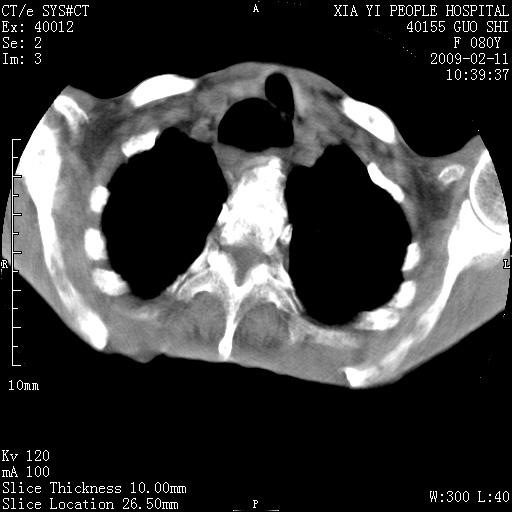

以下是引用随光逐影在2009-2-16 16:34:00的发言:[br]1)考虑右前纵隔皮样囊肿。2)双侧少量胸腔积液。

以下是引用zjzjr在2009-2-16 17:30:00的发言:[br]支持囊性畸胎瘤 双侧少量胸腔积液。